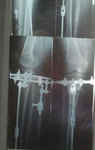

Рентген в 90 дней.

Здравствуйте, Галина! Сращение слабое, ждём рентген в 4 месяца.

Просьба, делайте рентген снимки правильно, как написано у Вас в рекомендациях: РЕНТГЕНОГРАФИЯ ОБЕИХ ГОЛЕНЕЙ С КОЛЕННЫМ СУСТАВОМ В 2-Х ПРОЕКЦИЯХ.

Доктору обязательно нужен коленный сустав!